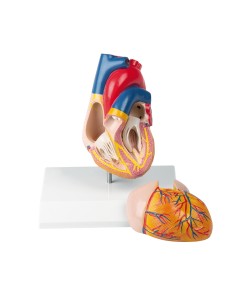

Dal cranio in 22 parti con incastri magnetici ai modelli di colonna vertebrale, da quelli di articolazioni a quelli di cuore, ogni pezzo della nostra collezione è progettato per un’immersione totale nello studio dell’anatomia umana. I nostri modelli, realizzati tramite scansioni di ossa vere, garantiscono un’esperienza tattile autentica e una fedeltà di peso quasi identica agli originali.

Essenziali per studenti e professionisti, i nostri modelli anatomici sono strumenti didattici che permettono di osservare le strutture anatomiche con precisione, eliminando la necessità di dissezioni o studi invasivi. Sono inoltre utili per spiegare ai pazienti le patologie, rendendo la comunicazione più efficace e risparmiando tempo prezioso.